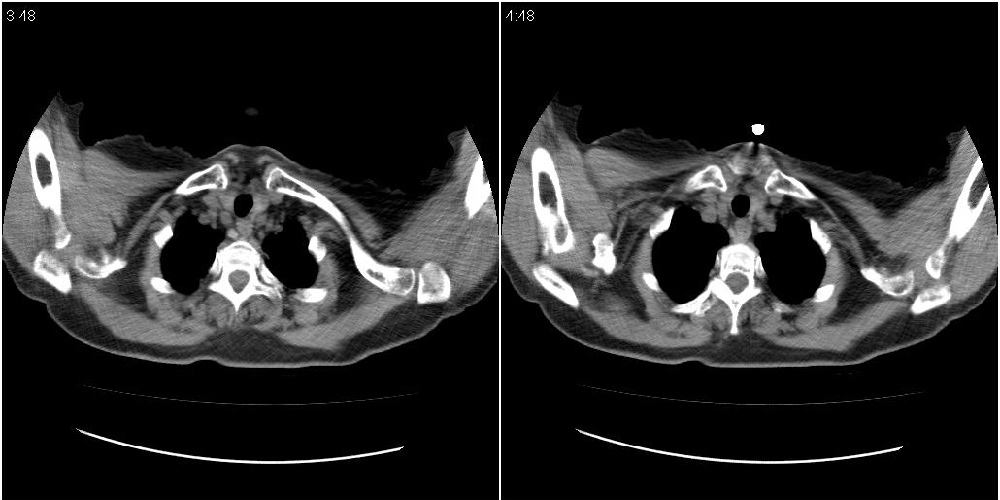

女性,72岁。去年9月份发现肺部病变,诊为肺结核并进行正规治疗至今,但复查后发现ct表现几乎没有变化。

右侧中叶支气管明显狭窄,建议行纤支镜检查!

右中间段支气管局限性狭窄,右中叶支气管亦稍显狭窄,但并未见明显占位表现,半年多了,无变化也许是好事,可能为炎性狭窄,建议继续随访。

右中叶炎性改变,支气管狭窄但较光滑,占位可能性不大。

右中间段支气管局限性狭窄,右中叶支气管亦稍显狭窄.